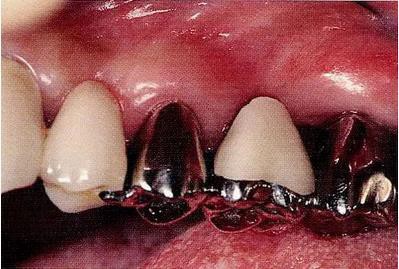

▼圖18-3

圖18-3 在其他醫(yī)院進(jìn)行了的修復(fù)處理。拔除了第一磨牙遠(yuǎn)中根的病例。近中根遠(yuǎn)中面殘留著一部分的邊緣。在這種部位很容易滯留牙垢,菌斑的控制會(huì)也很困難。